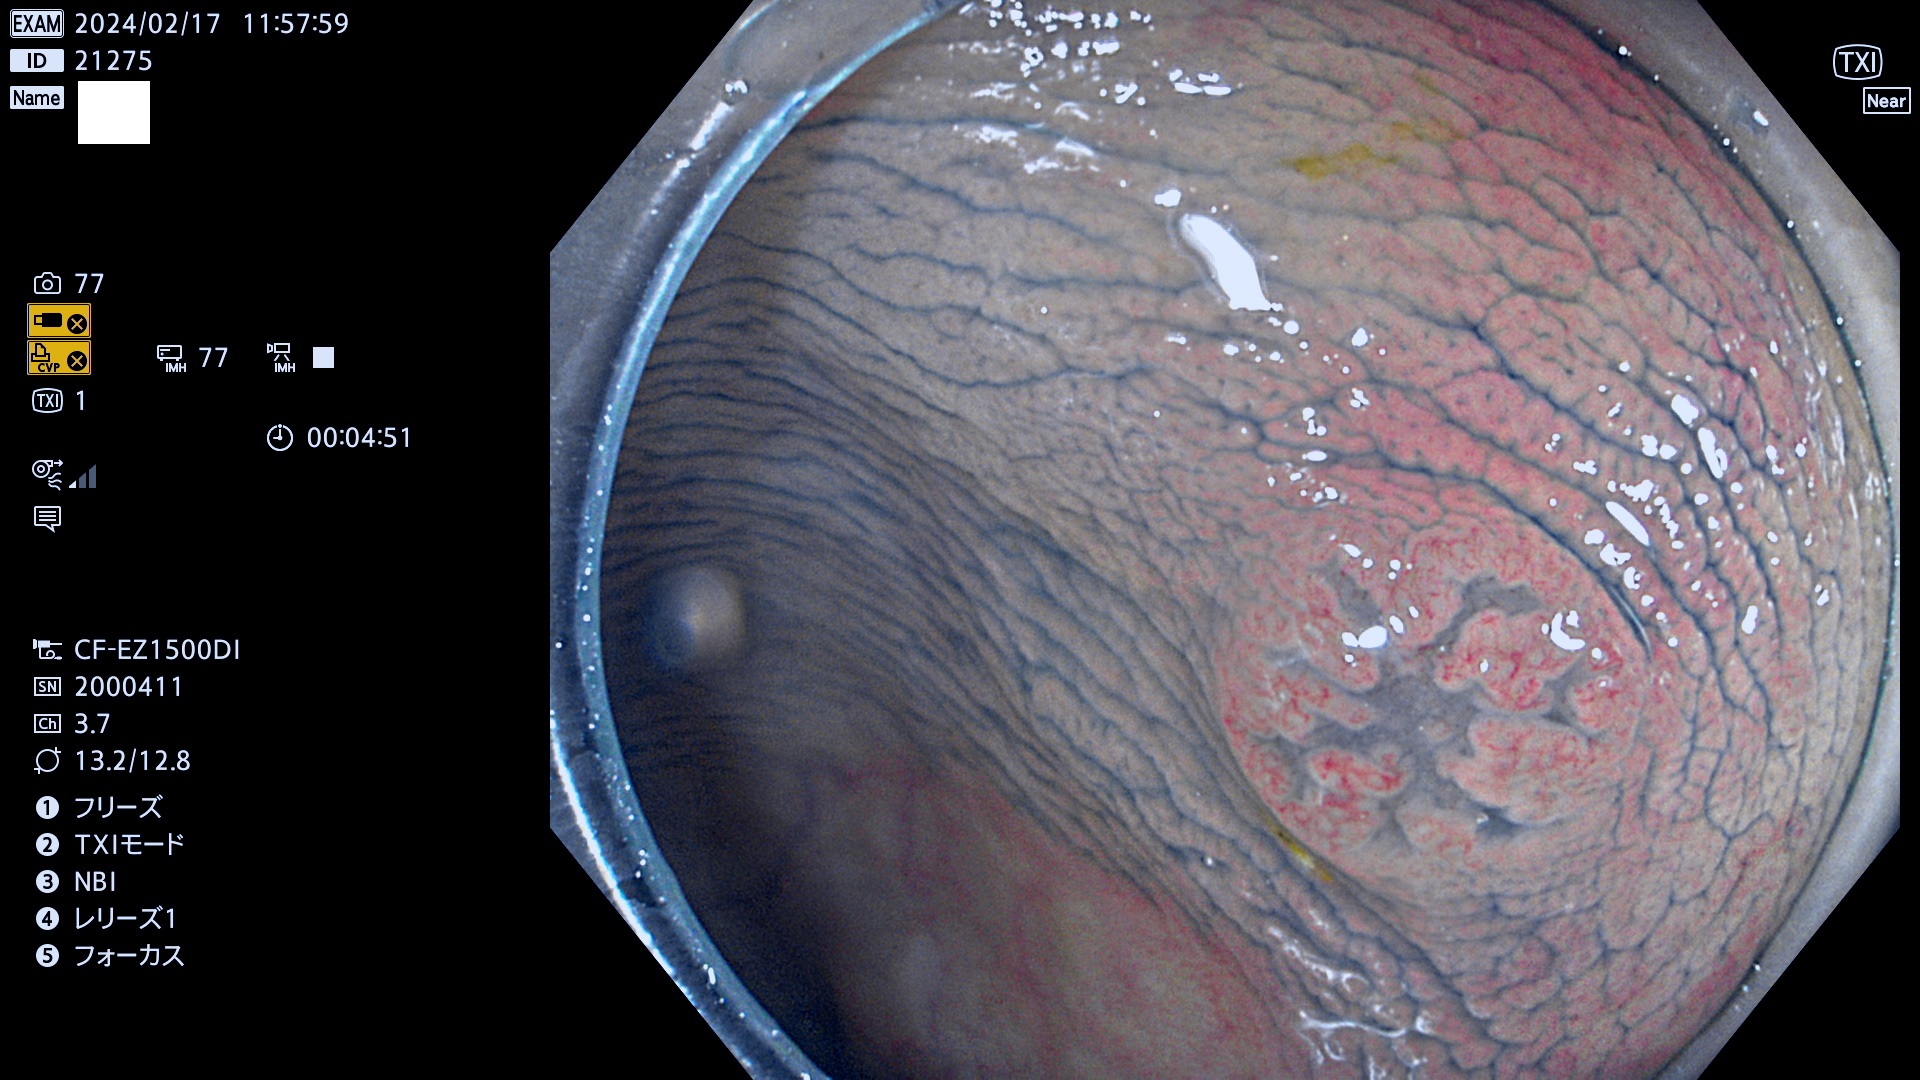

今週のUb、Uc型腺腫

表面型腺腫(Flat Adenoma)の中で、完全に平坦な物をUb、陥凹している物をUcと呼びます。平坦隆起型(Ua)よりも、発見が難しく危険な病変です。

毎週の検査(木・金・土・日)に発見されたUb、Uc型・腺腫を、その週の日曜の夜にUPし1週間、提示します。

抽出の対象期間 2024年2月15日(木)〜2月18(日)の4日間(40件の検査)10件 (10/40=25%)